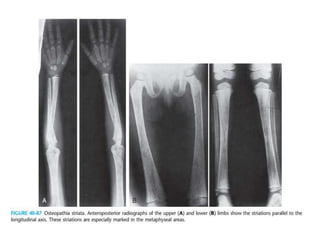

Antero-posterior radiograph

showing V shaped distal

femoral physis

Radial head dislocation

Lateral radiograph showing

posterior scalloping

of vertebral bodies

& shortened pedicles